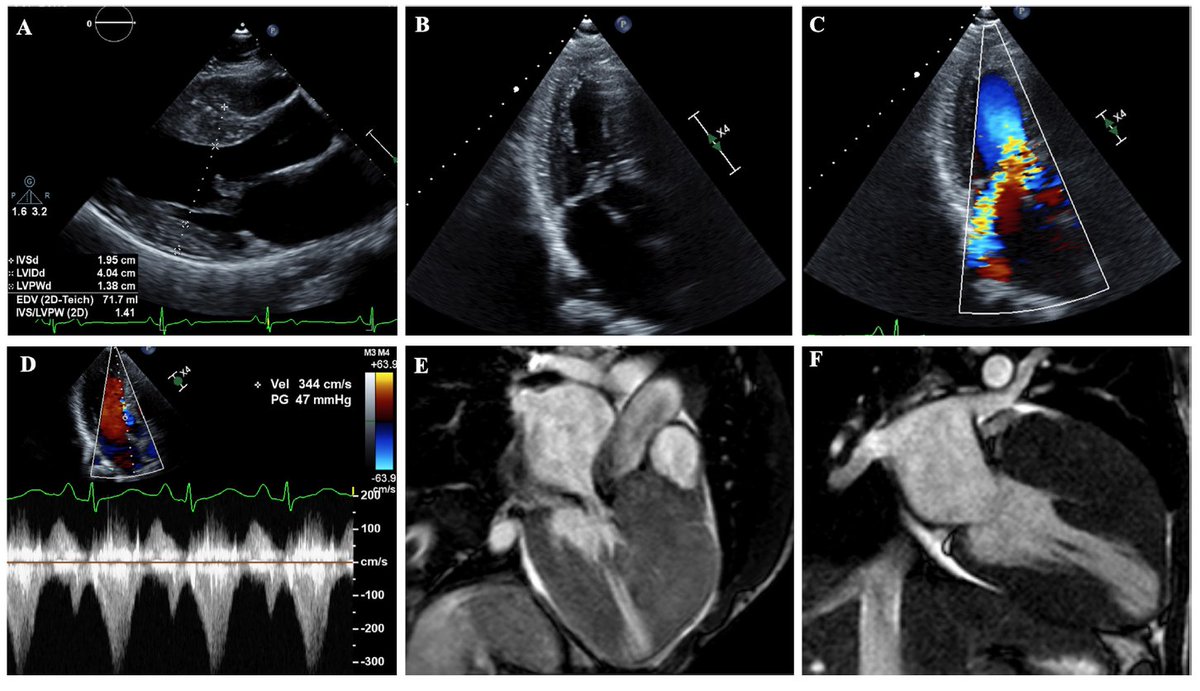

Our recent paper from

@CleClinicMD on advanced imaging for risk stratification in HCM@DesaiMilindY@agofava@ChetritMichael@AnastasiaSMihai@iamritu https://twitter.com/Heart_BMJ/status/1222796611094446080 …pic.twitter.com/wjWcK7UkuD